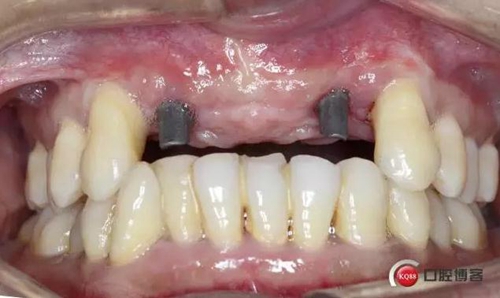

戴入修復(fù)基臺

戴牙完成